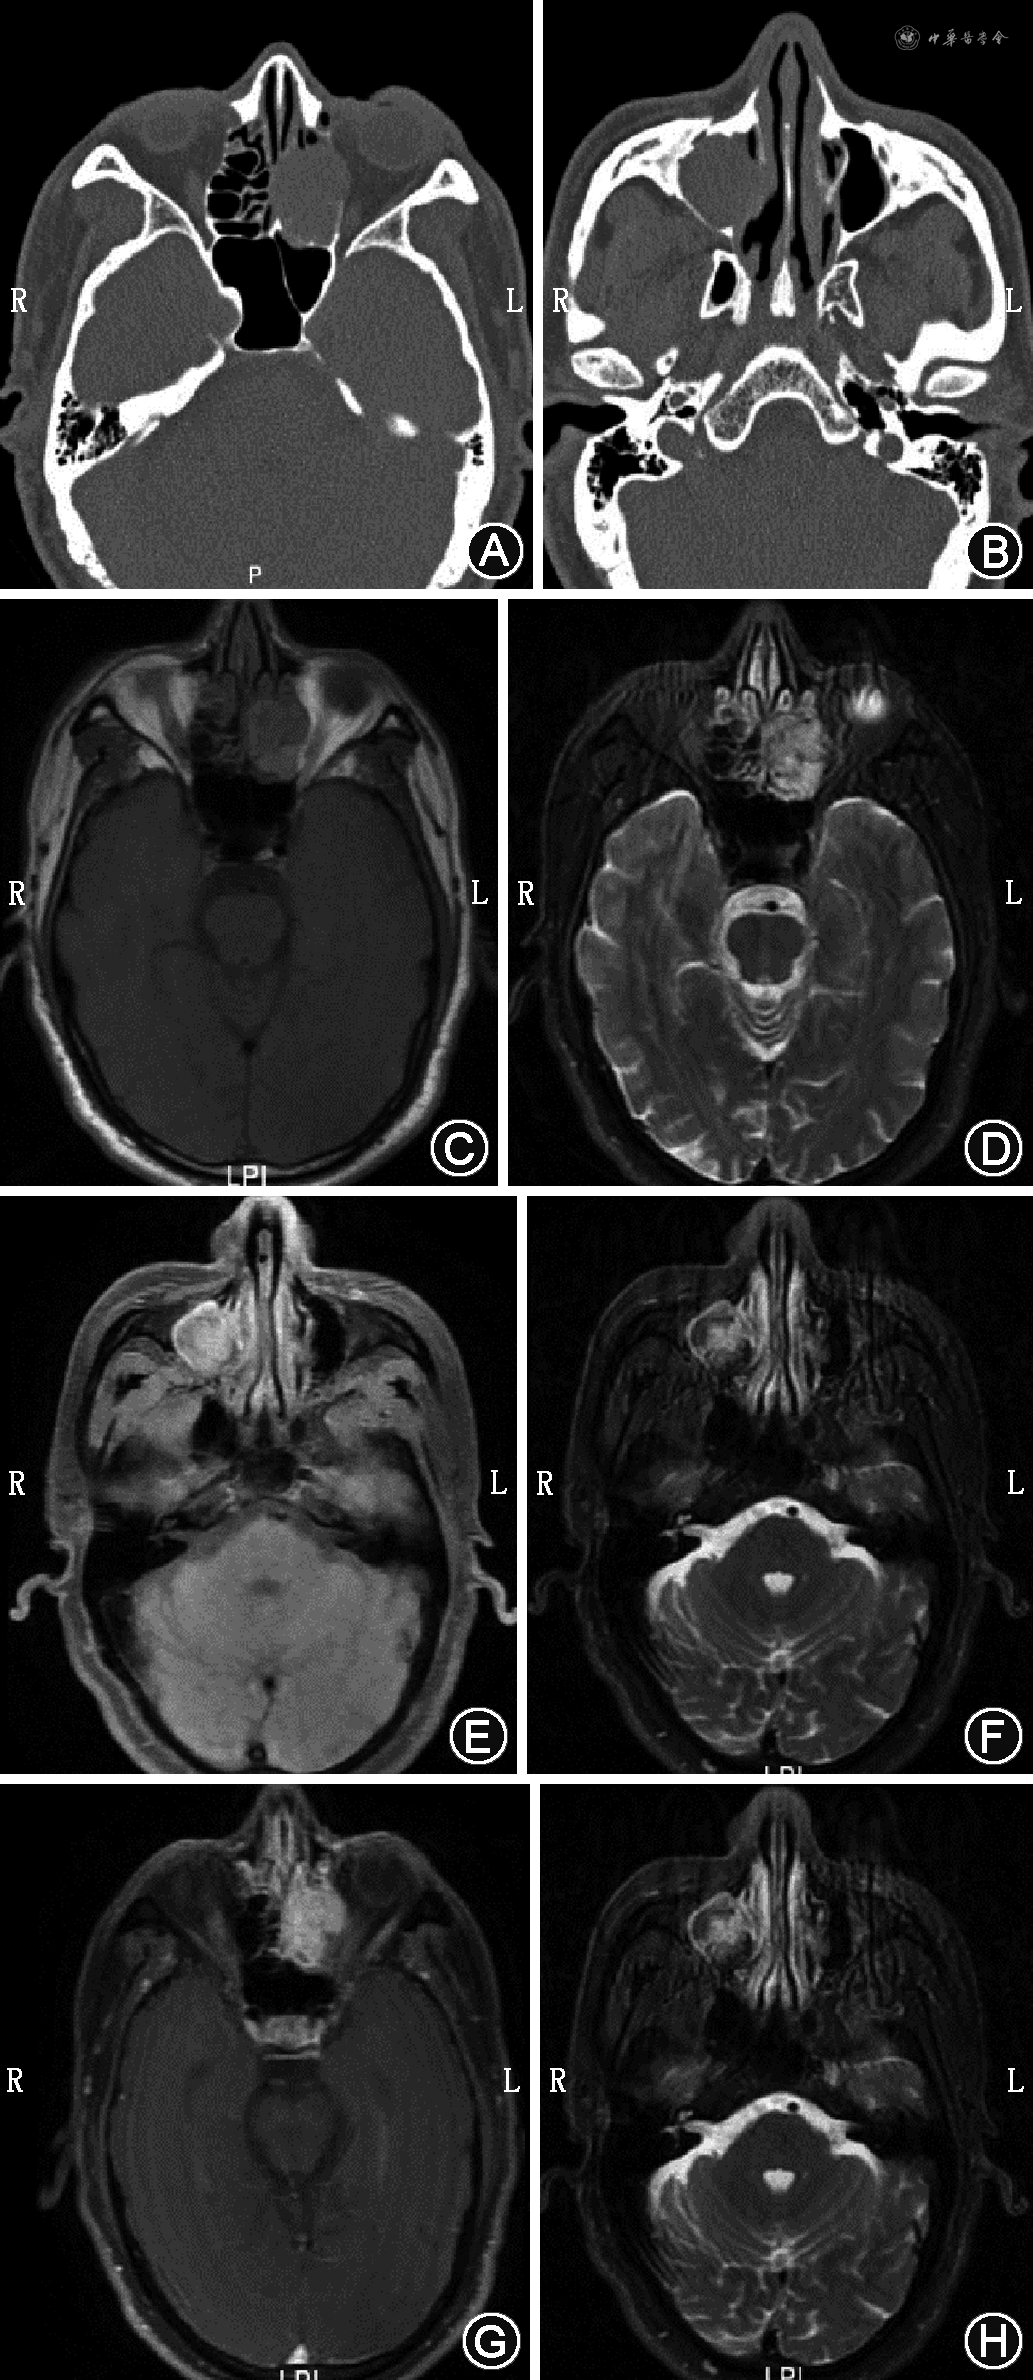

例1 患者男,61岁,因左侧持续性鼻塞伴淡黄色分泌物1月余来我院就诊。专科体格检查:外鼻无畸形,左侧鼻腔见新生物堵塞,各鼻窦区无压痛。鼻窦CT示左侧鼻腔内团块状软组织密度影,边界不清,周围骨质吸收破坏(图1A)。MRI提示左侧上颌窦、双侧筛窦、双侧额窦及蝶窦内斑片状长T1长T2信号(图1B、C),弥散加权成像(DWI)呈不均匀高信号,增强扫描呈明显不均匀强化(图1D)。入院后诊断为鼻腔肿物,取新生物病理回报其形态符合息肉。详细询问患者病史,患者于2005年因左肾透明细胞癌行左肾切除手术,考虑局部病理结果可能与实际病变存在差异,遂于全身麻醉下行手术探查。0°鼻内镜下见左侧鼻腔新生物,切除左侧钩突,开放上颌窦,低温等离子刀辅助下切除肿物,开放筛窦,见眶内壁骨质受损,低温等离子刀切除左侧眶内壁及部分脂肪组织。开放蝶窦,见蝶鞍及视神经管骨质破坏,电钻磨除部分骨质。开放额窦,见窦内充满新生物,切除肿物后,见左侧额窦后壁骨质破坏,部分硬脑膜裸露,取鼻中隔黏膜瓣修复。术后病理回报符合透明细胞性肾细胞癌转移,免疫组织化学(免疫组化)染色结果:CK(AE1/AE3)(+)、CAIX(+)、CD10(+)、CK7(-)、P504s(+)、TFE3(-)、PAX-8(+)、Vimentin(+)、Ki67(阳性率20%)。术后随访至半年时,患者出现左眼肿胀、视物模糊,复查MRI示双侧前组筛窦、双侧额窦、左侧上颌窦、双侧蝶窦内稍短T1长T2信号影,增强扫描可见强化,考虑为肿瘤复发(图2)。

例2 患者男,63岁,因头痛1个月、体检发现“鼻窦肿物”4 d就诊于我院,病程中患者有双侧交替性鼻塞,伴脓涕。患者3年前行左肾摘除术,术后病理回报为玻璃体细胞癌。专科体格检查:鼻内镜下鼻腔内未见明显新生物。鼻窦CT提示左侧筛窦、右侧上颌窦内团块状软组织密度影,边界欠清,密度不均匀,部分突入左侧眼眶内,右侧筛窦、左侧蝶窦及邻近左侧眶内壁、筛骨、蝶窦上壁骨质破坏,右侧上颌窦病灶部分突入右侧筛窦,邻近骨质受压变薄(图3A、B)。MRI示左侧筛窦及右侧上颌窦内不规则等T1稍长T2信号(图3C~F),DWI未见明显高信号,增强扫描不均匀中度强化(图3G、H)。全身麻醉下行手术探查,0°鼻内镜下见左侧中鼻道膨隆,切除钩突,开放上颌窦,切除筛泡基板,开放筛窦,见有暗红色新生物占位,触之易出血,完全切除肿物,颅底骨质完整,左侧眶纸板部分缺如,去除左侧眶纸板见眶内筋膜完整。于右侧下鼻甲前端行泪前隐窝入路,见上颌窦内充满肿物,呈膨胀性生长,界限尚清。切除右侧钩突,开放上颌窦口,完整切除窦内肿物。术后病理回报符合肾透明细胞癌转移。免疫组化染色结果:CK(AE1/AE3)部分弱(+)、CK7(-)、Vimentin(+)、CD10(+)、CAIX(+)、PAX-8(+)、Ki67(阳性率10%)、P504s部分(+)、TFE3(-)。术后随访9个月无复发。